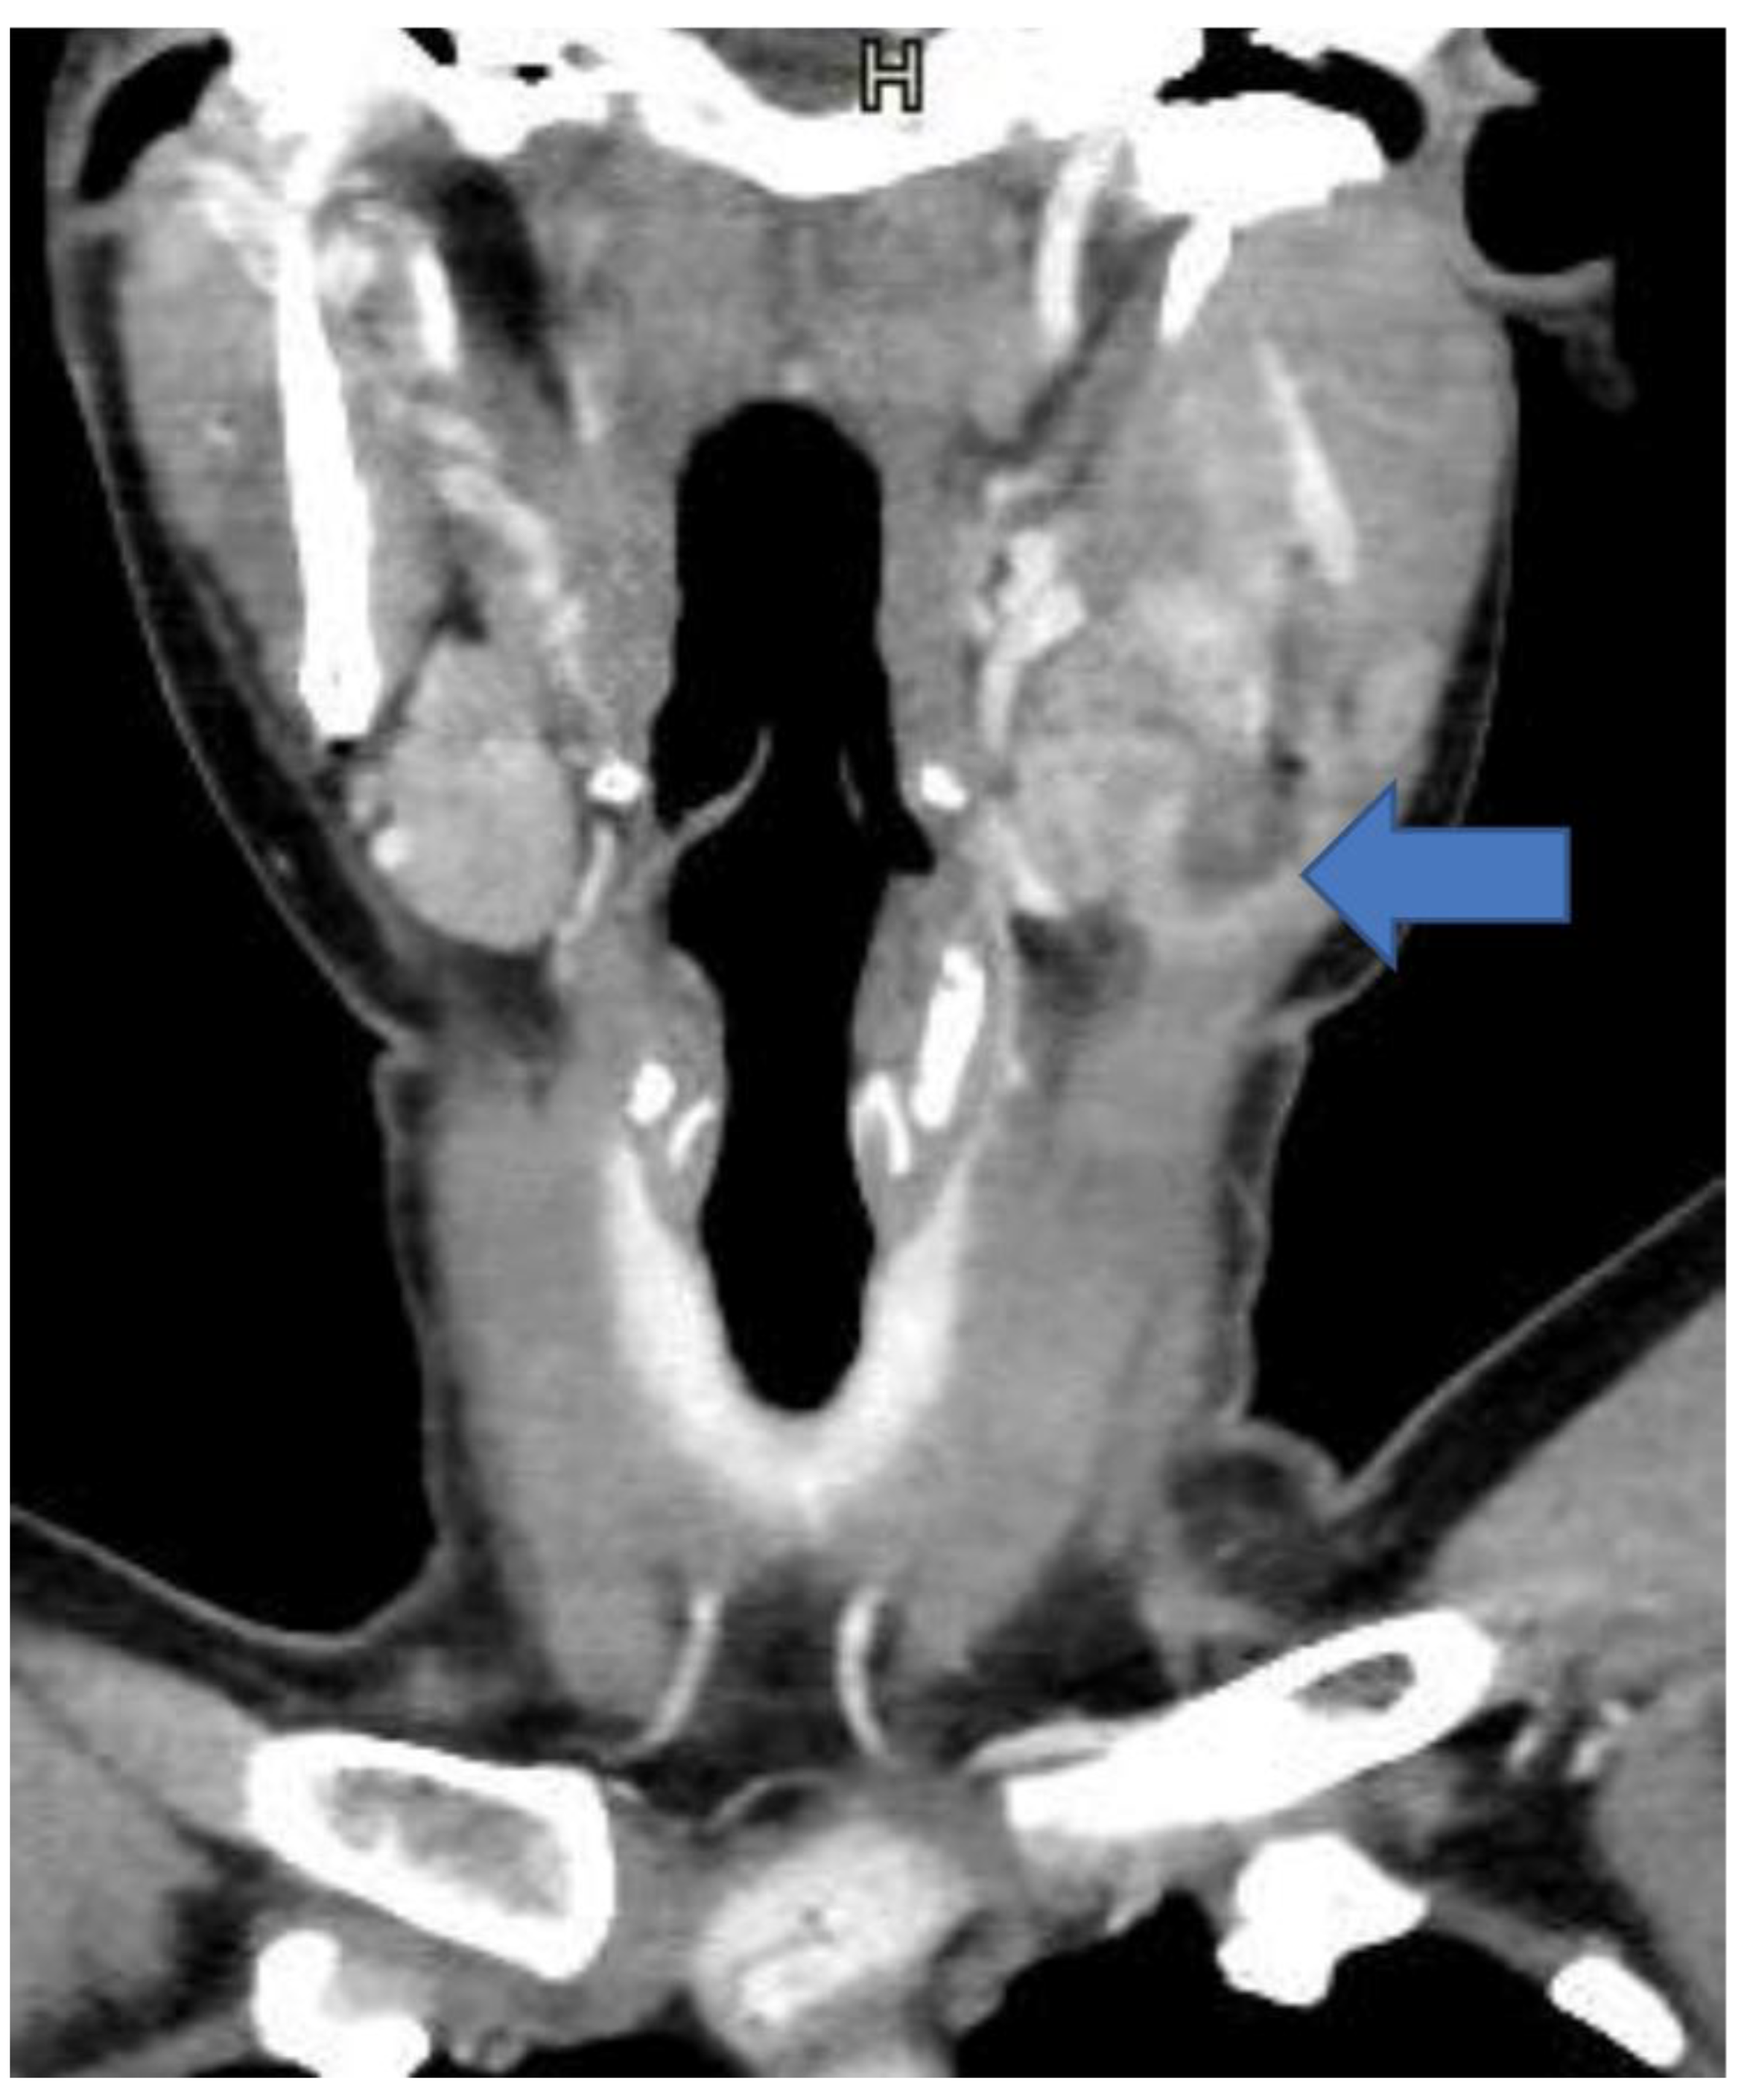

2. Detailed Case Presentation